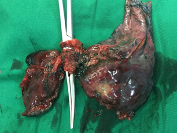

常规腔镜方面,以胸部肿瘤外科为主,开展肺叶、肺段、复合肺段/亚段切除、解剖性肺切除、袖状切除等手术,包括单孔到多孔等各种入路。在北京市较早开展微创食管癌切除,积累了丰富的经验。纵隔肿瘤方面,开展包括剑突下及其他入路胸腺切除、胸腺扩大切除,无名静脉成型等。同时结合锚丝定位、术前三维重建技术和荧光腔镜技术使手术安全高效。

目前主流的胸外科微创手术业务我科已达到全覆盖。包括但不限于:胸腔镜下肺叶、肺段、亚段、联合亚段、全肺、肺袖状切除术;单孔胸腔镜微创手术,Hook-Wire定位小结节精准切除手术,微创胸腹腔镜联合食管癌切除术,剑突下纵隔肿物切除术,达芬奇机器人辅助各类手术等几乎所有的胸外科先进微创的手术方式。

各类联合亚段切除术